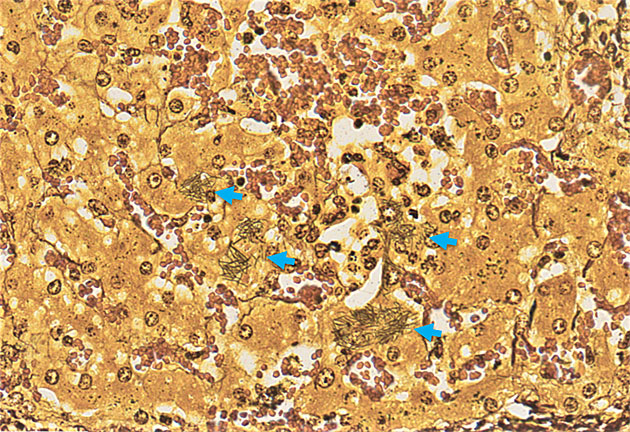

Bei der feingeweblichen (pathohistologischen) Untersuchung können ausgeprägte nekrotisierende, entzündliche Herde in den betroffenen Geweben festgestellt werden. Die Herde finden sich in erster Linie in der Leber und in geringerem Maße in Darmtrakt und Herzmuskel. Der Erreger kann mittels einer Spezialfärbung (Versilberung durch Warthin-Starry oder Giemsa-Färbung) nachgewiesen werden. Hierbei lassen sich die intrazellulären, filamentösen Bakterien von dem umliegenden Gewebe durch eine Silberfärbung differenzieren.

Bei der Sektion fielen ein ausgeprägter allgemeiner Ikterus, Blutungen in verschiedenen Organen und pathomorphologische Veränderungen in der Leber und im Darmtrakt auf. Die feingewebliche Untersuchung ergab massive multifokale Lebernekrosen sowie Nekrosen in der Herzmuskulatur und im Darm. Der Vorbericht und die pathologischen Befunde legten den Verdacht der Tyzzer-Krankheit nahe. Daher wurde die histologische Warthin-Starry-Spezialfärbung im Lebergewebe angewendet, um die obligat intrazellulären Bakterien nachzuweisen. Diese deckte eine massenhafte Ansammlung von intrazellulären, filamentösen Bakterien in der Nähe der Nekroseherde auf, typisch für Cl. piliforme.

Abbildung 2. Massenhaft, vorwiegend intrazelluläre, filamentöse Clostridium piliforme Bakterien (blaue Pfeile). Warthin-Starry, 25x